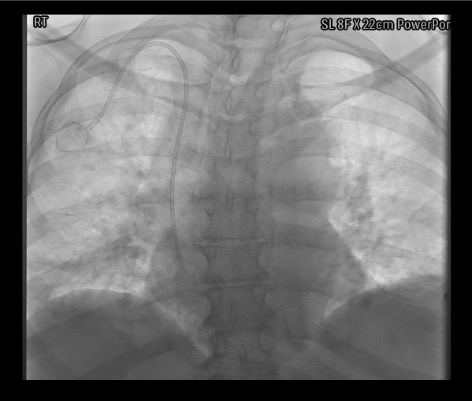

View final port position

Fluoroscopy showing implanted power port with catheter tip at SVC-RA junction